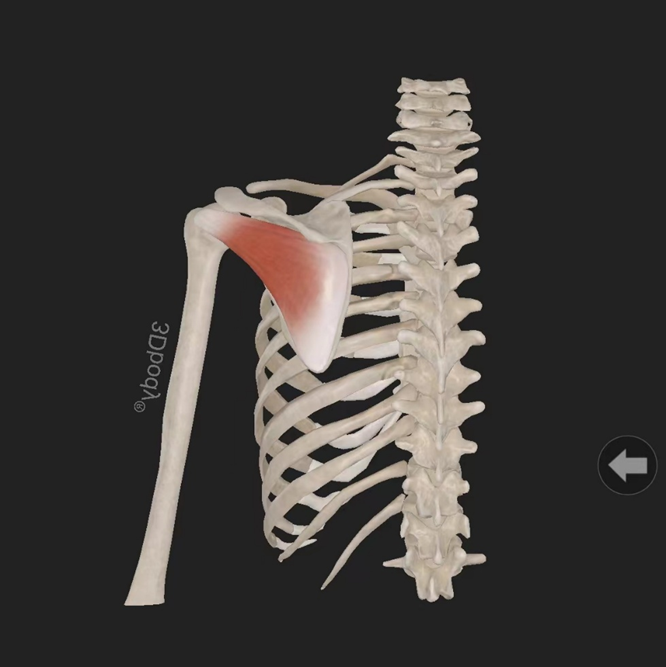

大圆肌:起自肩胛骨下角背面,止于肱骨小结节嵴。由肩胛下神经(C5—6)支配。作用:使肩关节内收、旋内、后伸。

小圆肌:起自肩胛骨外侧缘背面,止于肱骨大结节下部。由腋神经(C5—7)支配。作用:使关节旋外。

冈上肌:起自冈上窝,穿过肩峰和喙肩韧带,止于肱骨大结节上部部。由肩胛上神经(C5—6)支配。作用:使肩关节外展。

冈下肌:起自冈下窝内,止于肱骨大结节中部。由腋神经(C5—7)支配。作用:使关节旋外。

肩胛下肌:起自肩胛下窝(肩胛骨前面),止于肱骨小结节。由肩胛下神经(C5—6)支配。作用:使肩关节旋内、内收。